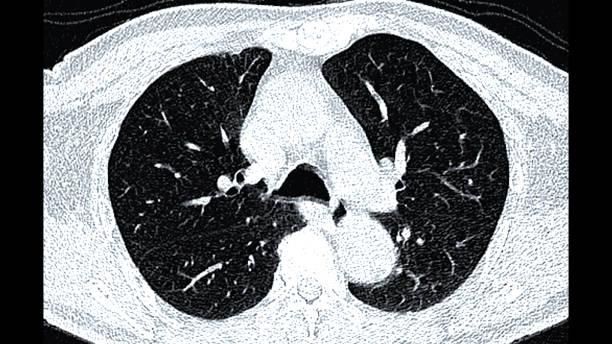

Chez des patients porteurs de nodules pulmonaires de 10–30 mm, la bronchoscopie guidée par navigation électromagnétique et imagerie 3D atteint une exactitude diagnostique de 79 %, non inférieure à la ponction‐biopsie transthoracique (73 %). Elle divise par neuf le risque de pneumothorax drainé ou hospitalisant, redessinant l’algorithme d’exploration des nodules périphériques à risque intermédiaire ou élevé de cancer.

Face aux millions de nodules découverts chaque année, deux techniques dominent : la ponction transthoracique (CT-TTNB), très sensible mais exposant à un risque de pneumothorax ≤ 25 %, et la bronchoscopie par navigation électromagnétique (NB) « inside-out », historiquement moins performante (rendement ≈ 70 %) mais plus sûre. L’arrivée d’imagerie intraprocédurales 3D (tomosynthèse, cone-beam CT) a revitalisé la NB, sans évaluation randomisée jusqu’ici.

L’essai multicentrique VERITAS, présenté au congrès annuel de l’American Thoracic Society et publié dans le New England Journal of Medicine, a randomisé 234 adultes (nodule 10-30 mm, probabilité prétest de cancer intermédiaire/élevée) entre NB ou CT-TTNB. À 12 mois, un diagnostic spécifique confirmé (malin ou bénin étiqueté) est obtenu chez 94/119 NB (79,0 %) versus 81/110 CT-TTNB (73,6 %). La différence absolue de +5,4 pts (IC à 95 : –6,5 ; 17,2) satisfait à la marge de non-infériorité de –10 pts (p = 0,003) sans supériorité statistique (p = 0,17).

L’exactitude ne varie pas selon la taille (10–20 mm vs 20–30 mm) ni la localisation lobaire. Les explorations NB ayant recours au scanner intra-opératoire affichent un taux de succès de 82 %, versus 72 % sans imagerie 3D.